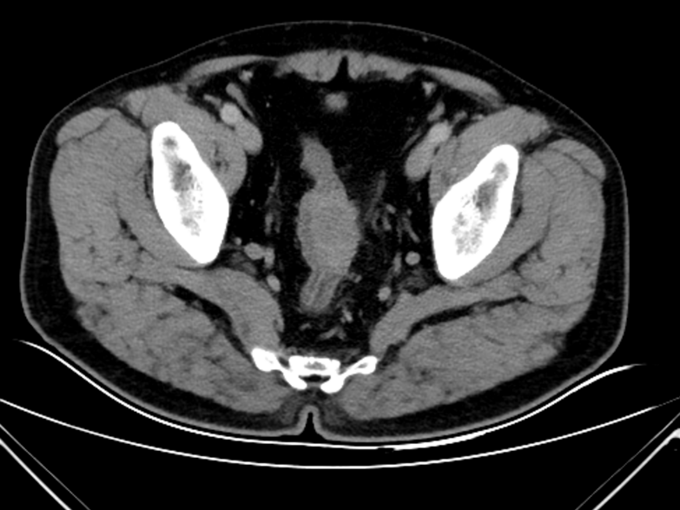

查体:腹平坦,未见胃肠型及蠕动波,未见腹壁静脉曲张。全腹软,未触及腹部肿块,压痛(-),反跳痛(-),肌紧张(-)。肝脾肋下未触及,Murphy’s 征(-),肝区叩击痛(-),移动性浊音(-)。肾区叩击痛(-)。肠鸣音正常,4次/分。肘膝位,肛门进指顺利,进指约7cm,未触及明确肿物,退指指套无染血。 辅助检查:马应龙肛肠医院肠镜检查显示:距离肛门60cm30cm见两枚大小约0.3*0.2cm息肉,表面光滑,广基、无蒂、无色泽略红,距肛门15cm处可见一半环行菜花样粘膜隆起。表面凹凸不平,出血、糜烂与污秽交织在一起,隆起向腔内生长,至管腔狭窄,镜身未通过,取病理5块。 术前腹部CT:乙状结肠下段肠壁增厚